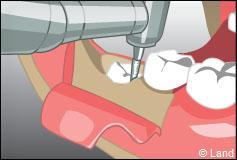

Certaines dents n’arrivent pas à faire leur éruption sur l’arcade correctement, présentent un accès difficile (dents de sagesses), ont des racines divergentes ou très courbées, ou sont considérablement abîmées (carie importante par exemple). Aussi elles restent souvent en partie ou totalement incluses dans l’os. On procède alors à une extraction chirurgicale.

L’intervention commence là aussi par une anesthésie locale, puis le chirurgien-dentiste procède à une incision de la gencive et à un dégagement du tissu osseux autour de la dent.

Parfois cette dernière est sectionnée pour ne pas traumatiser l’os souvent responsable de suites opératoires douloureuses.